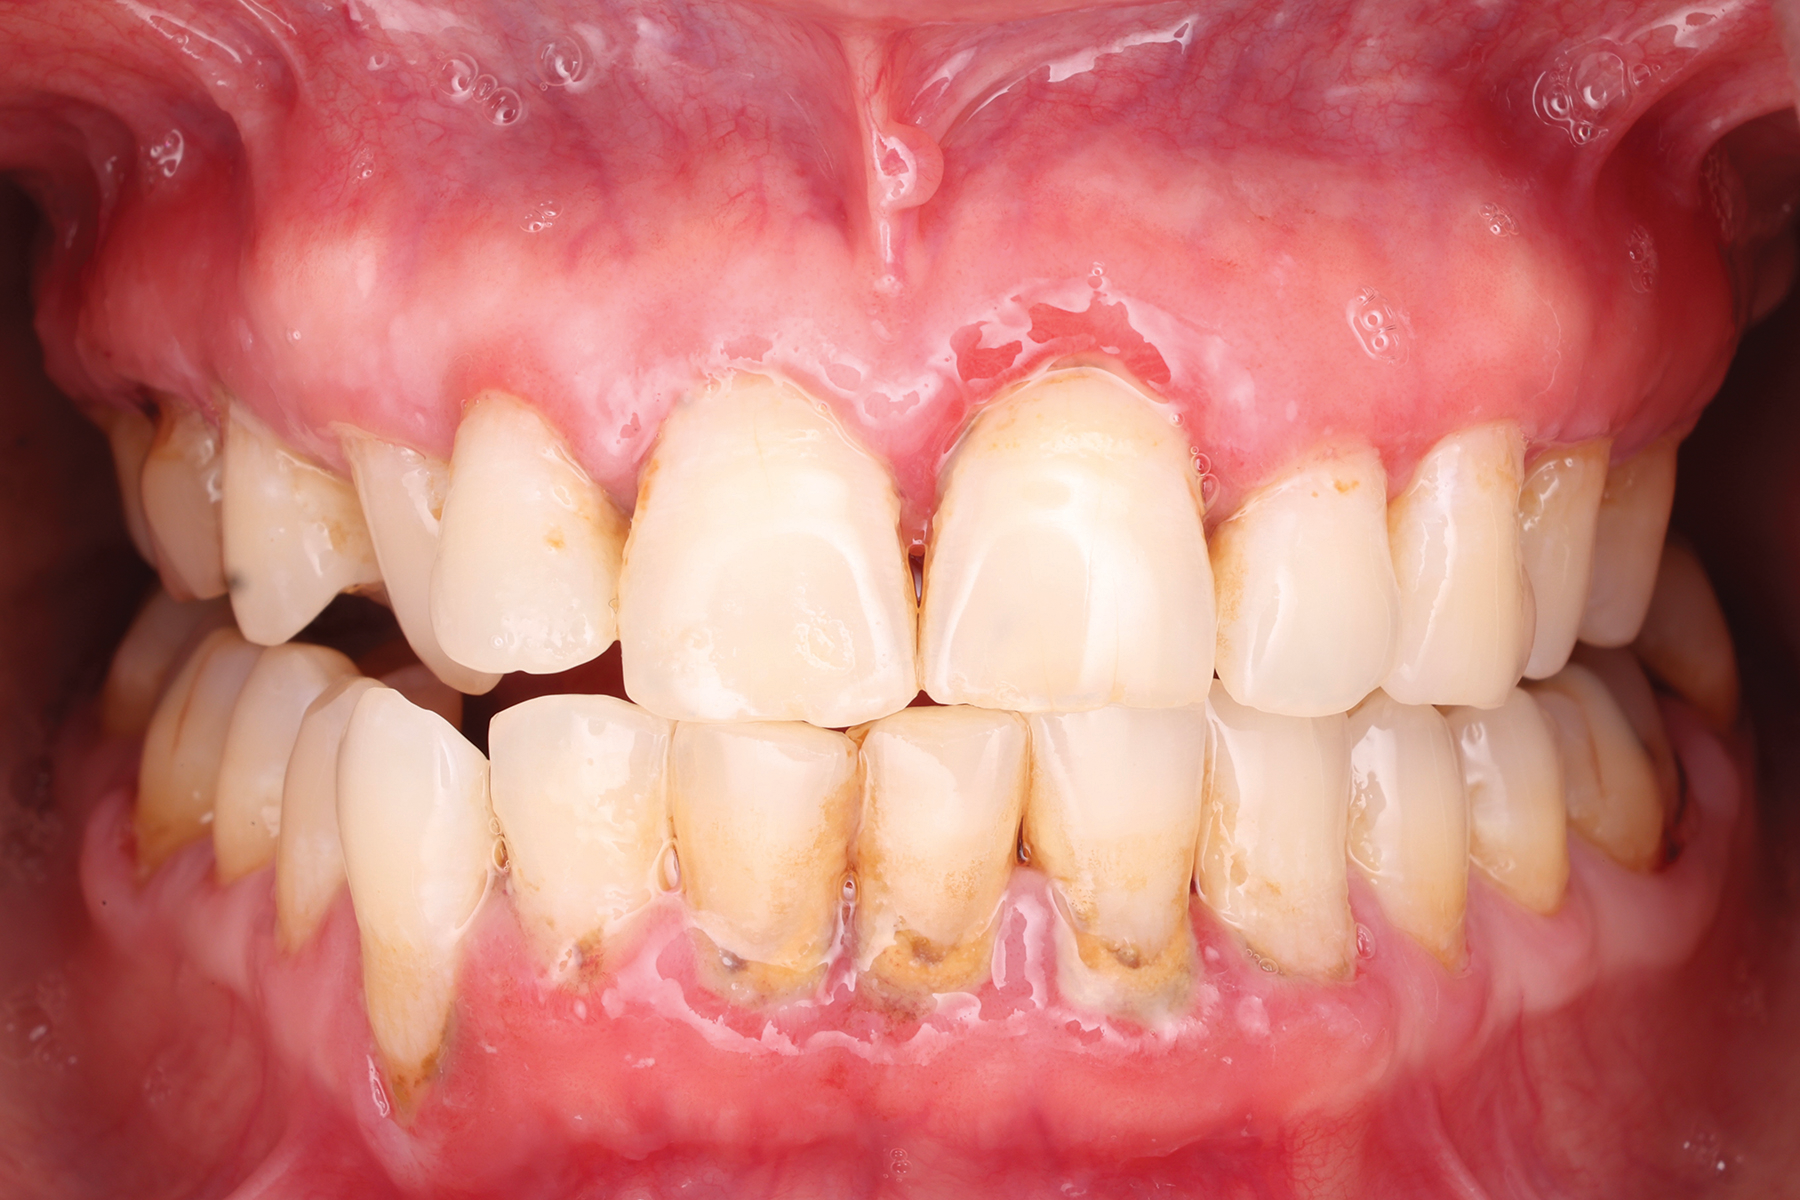

Erythematous/erosive/atrophic: Painful, red, raw mucosa, often on the gingiva (desquamative gingivitis), coexisting with reticulated areas (Figure 1).

Fig 1. Erosive lichen planus in a 47-year-old African American female patient. Erythematous, ulcerated lesions could be visualized at the gingival margin in both the maxilla and mandible. The patient reported significant discomfort associated with these lesions and aversions to acidic and hot foods due to pain after consumption.